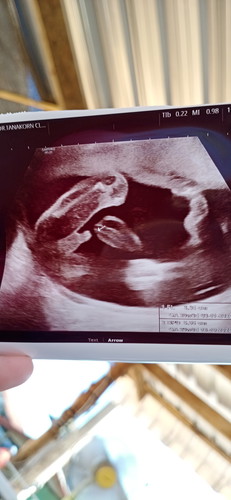

ลุงหมอบอกว่าหนูนอนเล่นจู๋ตัวเองอยู่

แม่นี่ขำไม่หยุดเลยลุงหมอก็ขำไม่หยุดเหมือนกันจู๋ใหญ่เชียวลูกเอ้ย

ดูอย่างไรอะคะ เล็กๆขาวๆ ใช่ไหมค่ะ เคยถามหมออยู่ค่ะ ว่าดูไม่เป็น หมอบอกว่าหากคุณแม่ดูเป็น คุณหมอจะตกงาน

จู๋ชัดมากค่ะแม่ ยินดีด้วยจ้า

ชัดมากค่ะ55555 เอ็นดูจังงงง☺️